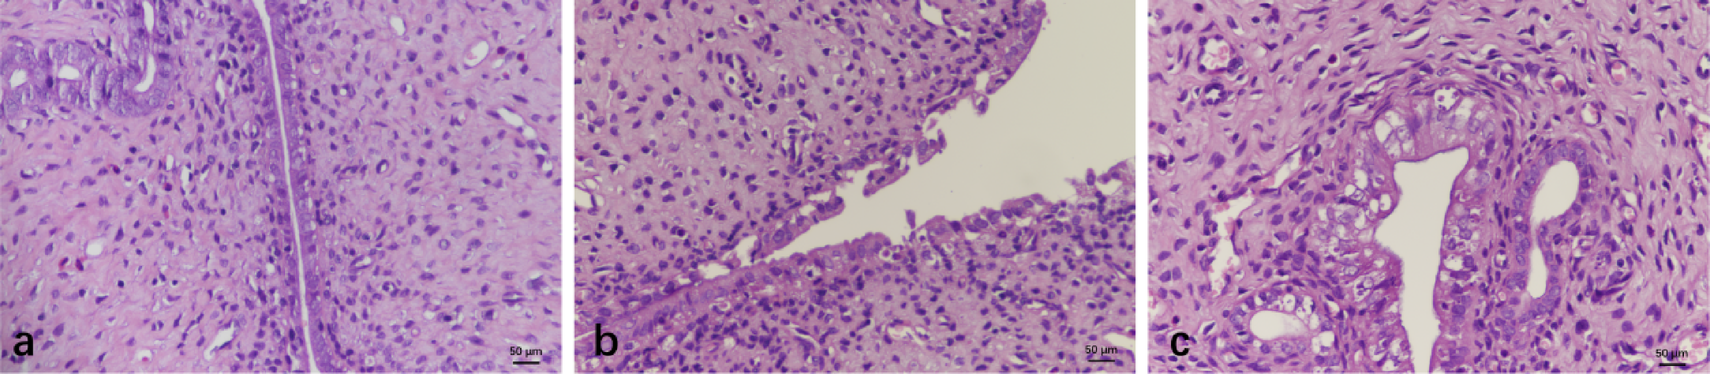

H&E Staining of Endometrial Samples. Endometrium of the normal group (a). Endometrium of the model group (b). Endometrium of the UC-MSCs group(3c). All images are captured at a magnification of ×400. Scale bar: 50 μm.